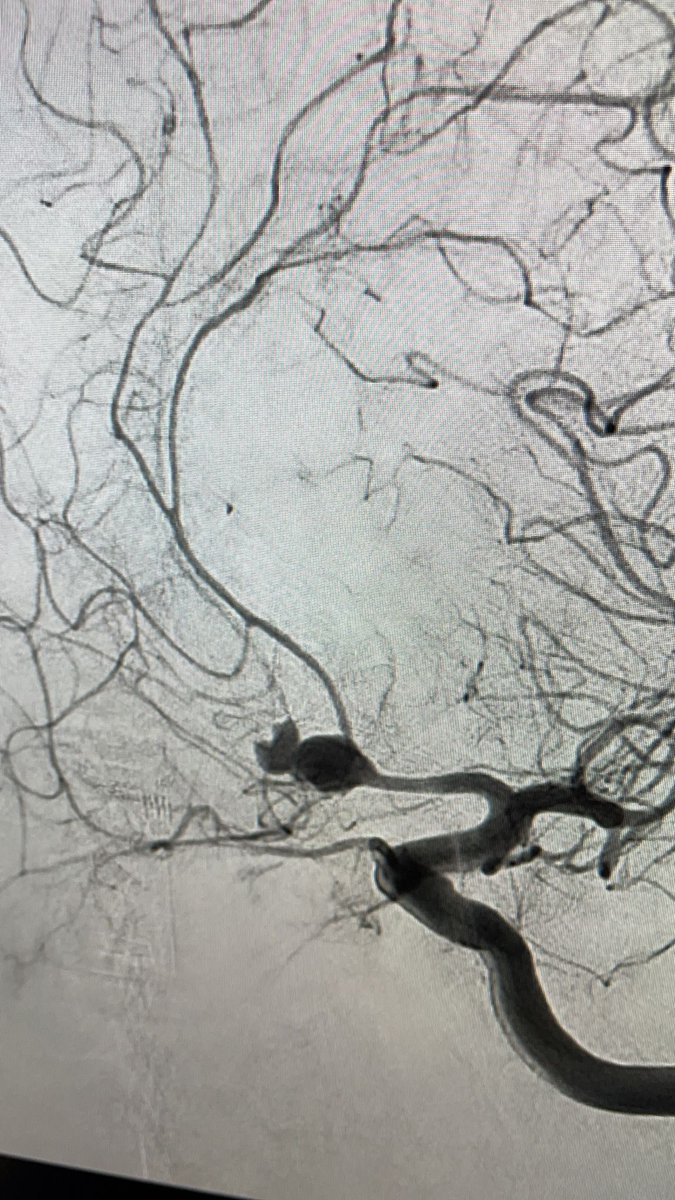

El Dr. Carlos Pérez@Justcharly9, nos resume en menos de 15 minutos los dos principales ensayos clínicos que comparan tratamiento Endovascular VS Quirúrgico (ISAT, IBRAT) de aneurismas rotos.